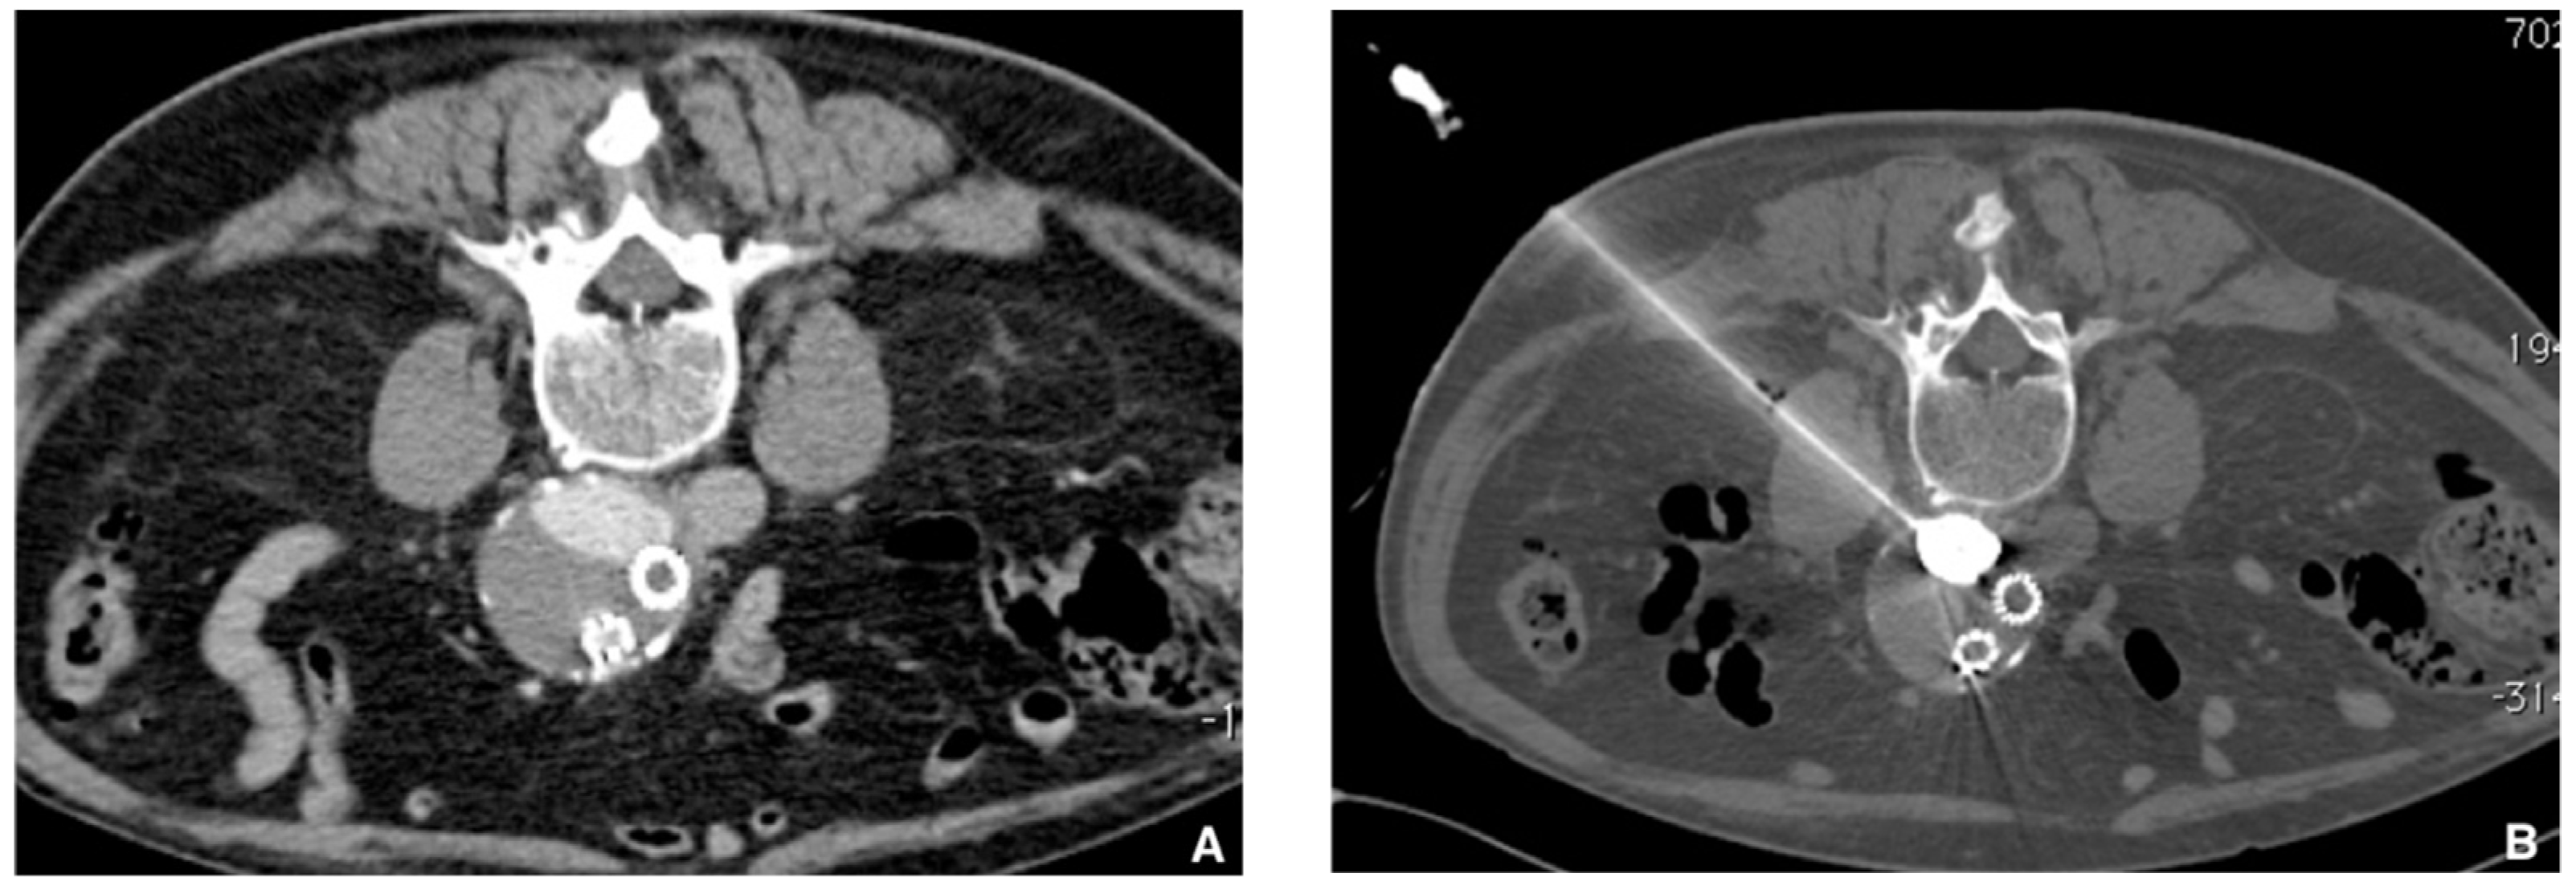

Figure 6. Prophylactic selective embolization of a large angiomyolipoma of the right kidney. (A) Angiography shows two feeding arteries to the angiomylipoma which is hypervascular. (B) Final control after selective and fast embolization of the two arterial branches with a Glubran®2/Lipiodol® mixture of a 1:6 ratio. (C) Computed tomography scan at day 14 showing lipiodol uptake by the angiomyolipoma which is totally devascularized.

Jcm 10 04320 g006